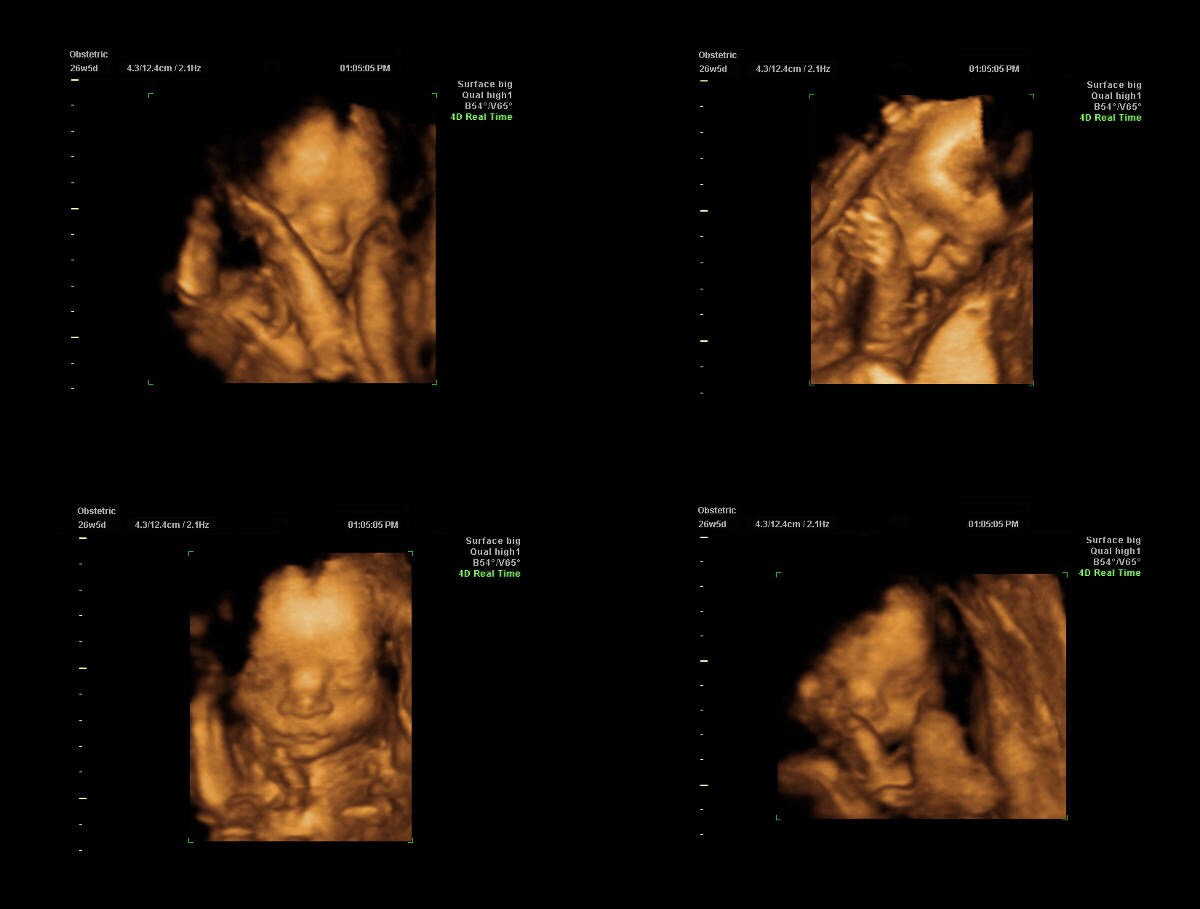

L’ecografia del secondo trimestre di gravidanza viene anche detta “morfologica”, dal greco morfè che significa forma: permette infatti di ottenere grazie all’uso di ecografi sofisticati straordinarie immagini in 3D e 4D del feto, che permettono innanzi tutto al ginecologo di osservare tutti gli organi del feto e valutarne forma e dimensioni, allo scopo di escludere circa il 60% delle possibili malformazioni fetali (alcune malformazioni non sono visibili se non al terzo trimestre, quando gli organi interessati hanno completato il loro processo di maturazione).

Questa ecografia, però, ha anche un bellissimo risvolto emotivo: consente infatti di avere una primissima “foto ricordo” a colori del proprio figlio, ne permette di visualizzare i tratti del viso ed addirittura i movimenti come uno sbadiglio, una smorfia od osservarlo mentre si succhia il pollice o gioca con il cordone ombelicale .